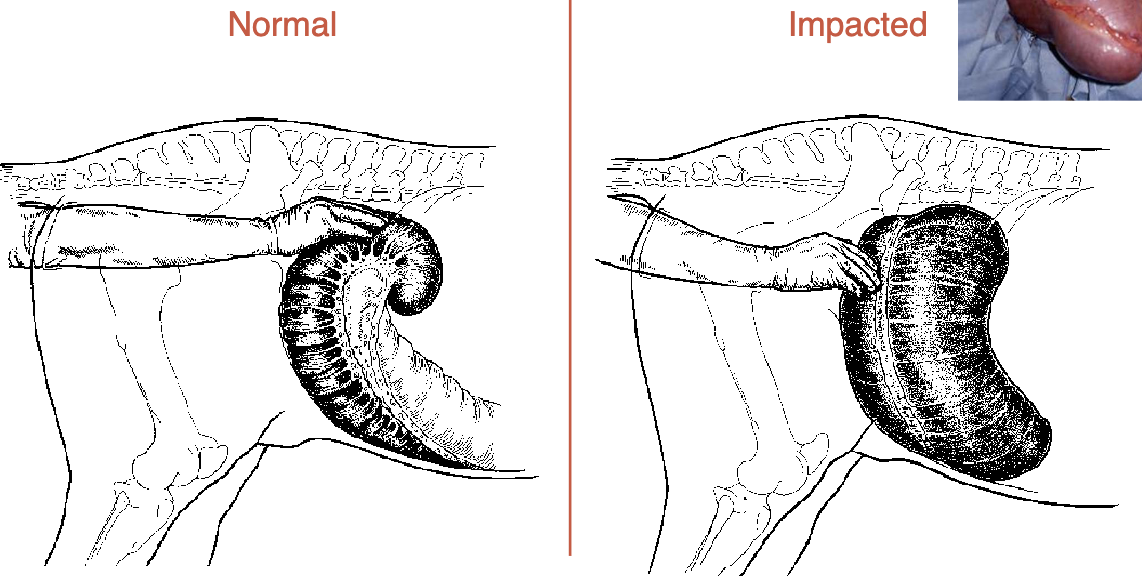

left dorsal displacement is aka

nephrosplenic entrapment

right dorsal displacement

pelvic flexure is high and on R side (normally low and L)

what is a large colon volvulus

twist on mesentery (location of blood vessels, cuts off supply & colon dies)